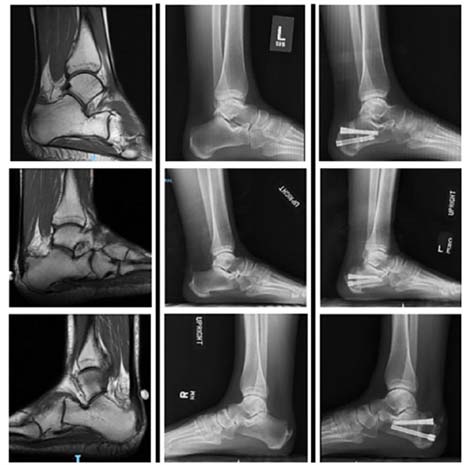

Radiation Exposure in Percutaneous Zadek Osteotomy vs Open Haglund Resection: A Retrospective Comparative Study.

Foot Ankle Orthop. 2026 Mar 10;11(1):24730114261425951. doi: 10.1177/24730114261425951 Preston Harrison, Sarah Hall Kiriluk, John O’Keefe, Harrison Lapin, Moawiah Mustafa, Shawn Guirau, Kevin Lee 4, Oliver N Schipper, J Benjamin Jackson III, Tyler A Gonzalez

PMCID: PMC12979876  PMID: 41836139

Comparing patient reported outcomes and complications following open versus minimally invasive double and triple arthrodesis for rigid flatfoot deformity: A retrospective analysis.

Fiore PI, Kiriluk SH, Harrison P, Schacht L, Montagna A, Gonzalez TA, Vulcano E. Foot Ankle Surg. 2025 Dec 24:S1268-7731(25)00292-9. doi: 10.1016/j.fas.2025.12.006. Online ahead of print.

PMID: 41469320